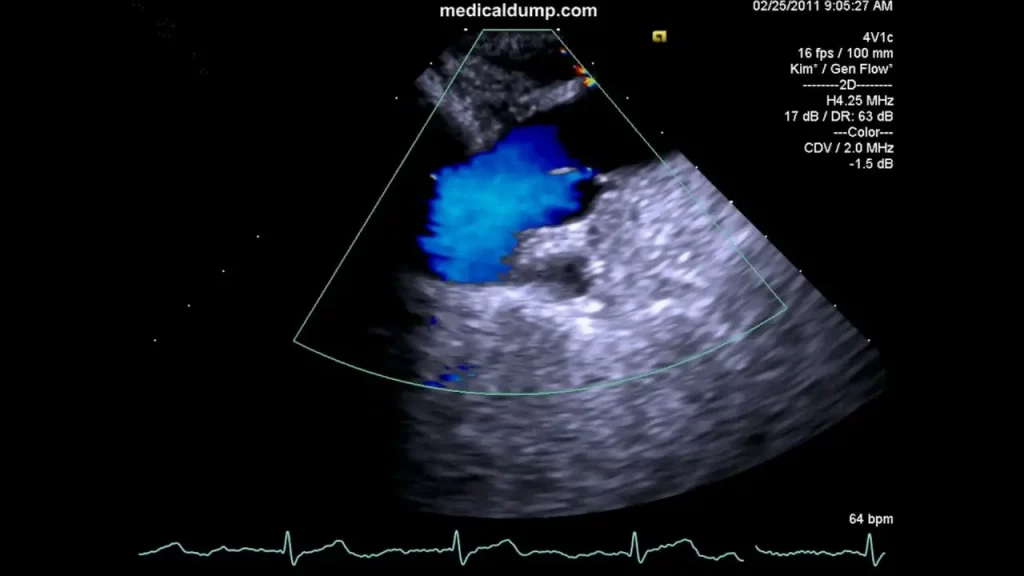

اکو قلب جنین یا Fetal Echocardiography نوعی سونوگرافی تخصصی است که به پزشکان امکان میدهد ساختار و عملکرد قلب جنین را در دوران بارداری با دقت بالا بررسی کنند. در این روش، دستگاههای پیشرفته با استفاده از امواج فراصوت تصویری دقیق از قلب، بطنها، دهلیزها، دریچهها، عروق اصلی و حتی ریتم قلب جنین ایجاد میکنند. به همین دلیل، اکو قلب جنین یکی از ابزارهای حیاتی برای تشخیص زودهنگام مشکلات قلبی محسوب میشود.

- کیفیت تجهیزات: دستگاههای پیشرفته با قابلیت Doppler و تصویربرداری سهبعدی دقت تشخیص را بسیار افزایش میدهند. به همین دلیل مراجعه به بهترین مراکز اکو قلب جنین اهمیت زیادی دارد.

ویستان با گردهم آوردن پزشکان متخصص در حوزه قلب کودکان، زنان و زایمان و سایر رشتههای مرتبط، امکان بررسی تصاویر اکو را به صورت تیمی و دقیق فراهم میکند. این همکاری چندتخصصی باعث میشود کوچکترین ناهنجاریها شناسایی و بررسی شوند، امری که بسیاری از والدین هنگام جستجو برای بهترین مراکز اکو قلب جنین به آن اهمیت میدهند. - تجهیزات پیشرفته تصویربرداری:

کلینیک ویستان از دستگاههای بهروز با قابلیت Doppler و تصویربرداری سهبعدی و چهاربعدی استفاده میکند تا ساختار قلب و جریان خون جنین با وضوح بالا قابل مشاهده باشد. این سطح تجهیزات، دقت تشخیص را به حداکثر میرساند. - رزرو نوبت آسان و دسترسی سریع: